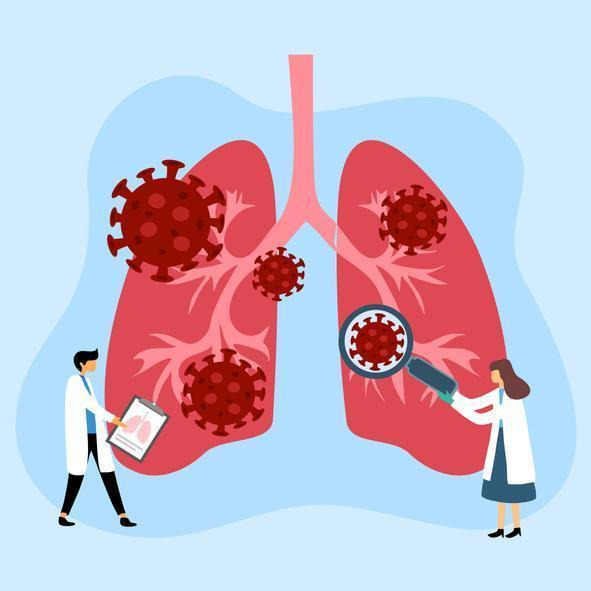

2. 폐암 검사 방법

폐암 검사는 다양한 방법으로 이루어지며, 조기 발견을 위한 정기적인 검사가 중요합니다. 여기에서는 주요 검사 방법에 대해 설명하겠습니다.

- 기관지 내시경 검사: 내시경을 통해 폐와 기관지를 직접 관찰하며, 필요시 조직을 채취하여 검사합니다. 암의 위치와 상태를 정확하게 확인할 수 있어 진단에 큰 도움이 됩니다.